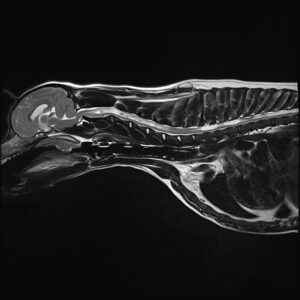

An MRI scan showed that Teddy had hydrocephalus – a condition that causes a build-up of excess cerebrospinal fluid (CSF) in the brain – and also a severe syringomyelia (fluid-filled cavities) of the spinal cord.

He has continued to do well and his postoperative MRI at 5 weeks after surgery show that the syringomyelia is mostly resolved and the ventricles are much smaller.